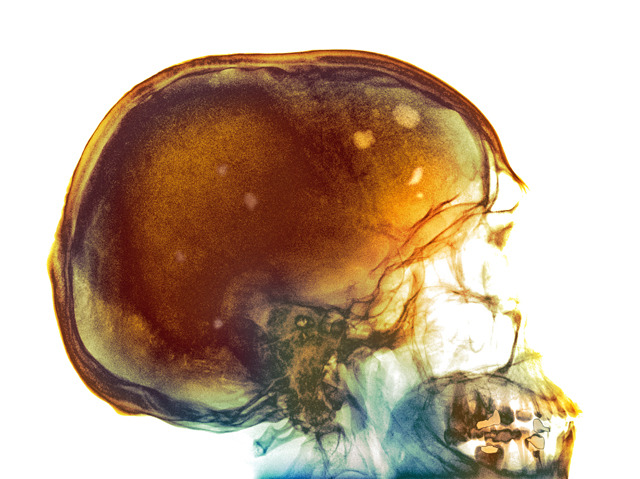

Therapies for stopping the spread of cancer usually target malignant cells but another approach is to make healthy tissue less vulnerable to invasion. In clinical trials, a substance called olaptesed pegol is being tested as a treatment for multiple myeloma, a type of cancer that forms bone tumours – like those seen here, as yellow and light brown patches, in a coloured X-ray image of a patient’s skull. Scientists designed olaptesed pegol to disable a protein called SDF-1, which in healthy bone marrow behaves rather like the Pied Piper, attracting certain cells to new locations. Suspiciously high levels of SDF-1 were found to be present near the site of myeloma tumours in experimental mice and blocking it seems to have made the bone marrow less alluring to malignant cells, slowing the progress of the cancer and extending the lifespan of the mice.